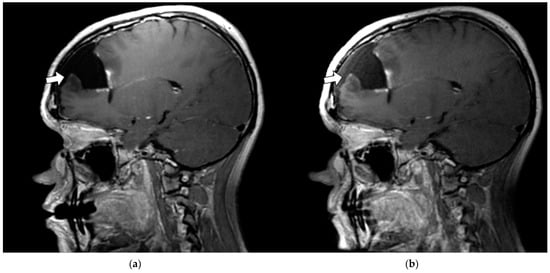

3.3.1. Margin Delineation